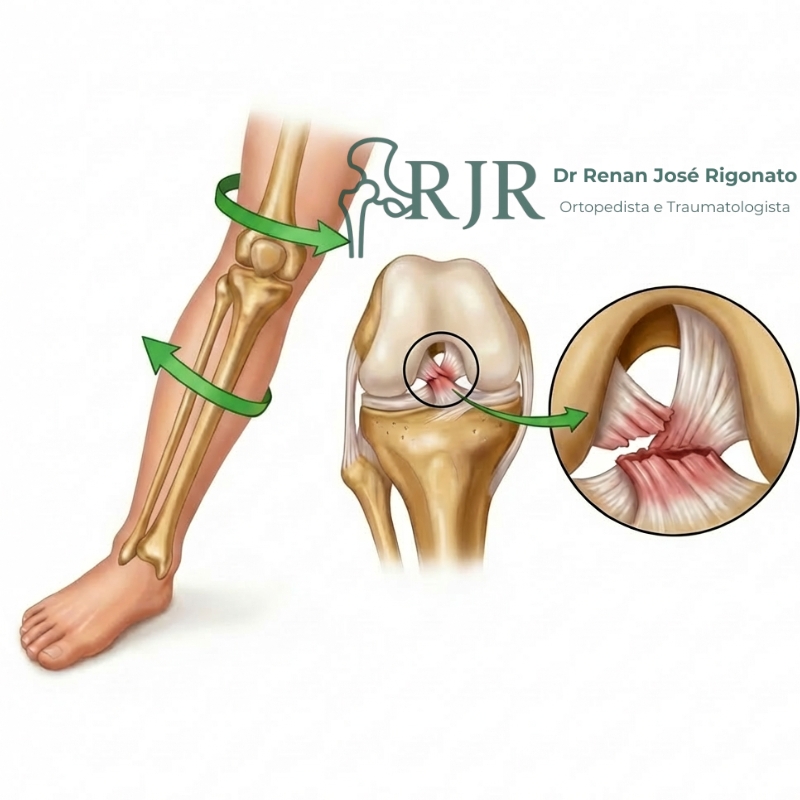

Lesões ligamentares

Os ligamentos são estruturas fundamentais para a estabilidade das articulações. Quando lesionados, podem causar dor, inchaço e insegurança ao movimentar. O diagnóstico preciso e o tratamento adequado ajudam a restaurar a função e prevenir novas lesões